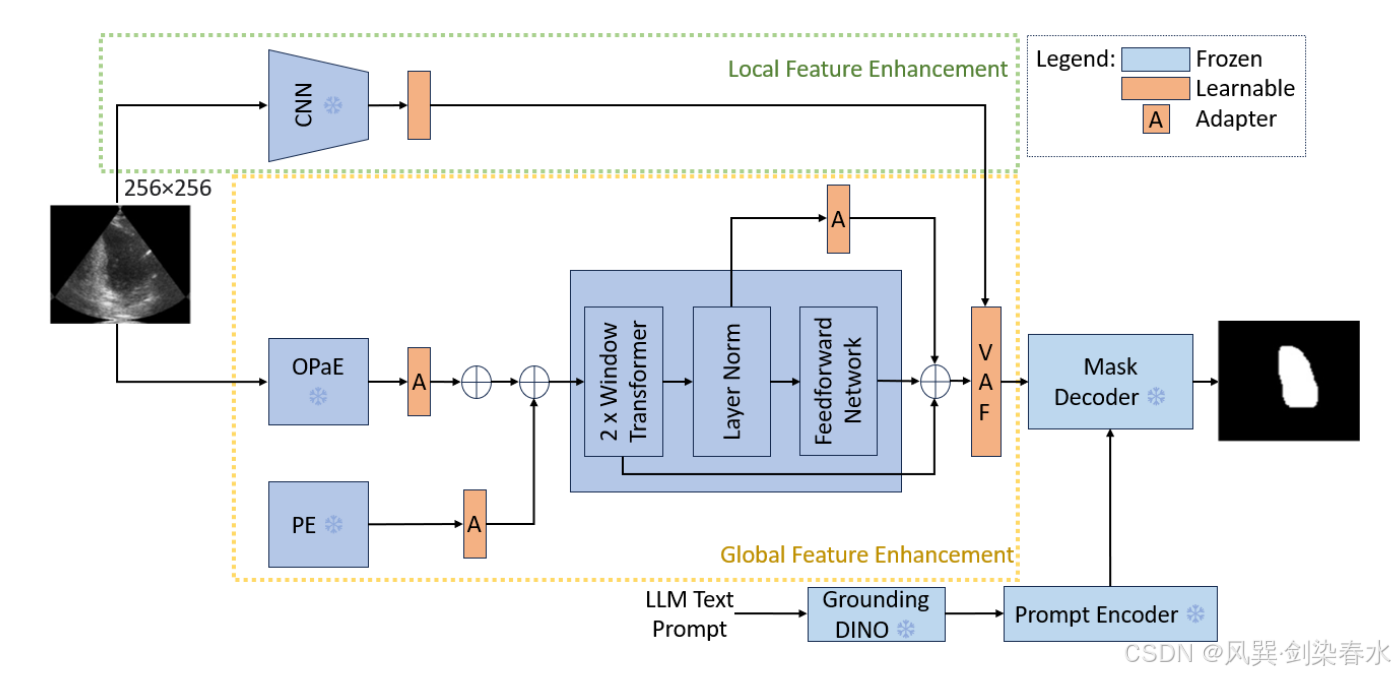

本文使用 Adapter (在 CNN 的情况下使用全连接层)来增强超声分割的局部和全局特征。“OPaE” 指重叠的 patch 嵌入,“PE” 指位置嵌入。

Figure 2 | CC-SAM 的概述:

3.1、具有 Adapters 的冻结主干

本文增强了 SAM 的图像编码器(ViT分支),通过引入了一个位置 adapter 和五个特征 adapters,以更好地适应更小的输入和医疗图像。这些 adapters 可以用更少的参数有效地微调 ViT 分支。

位置 adapter:修改位置嵌入以匹配嵌入的序列分辨率,它首先使用最大池对这些嵌入进行降采样,然后通过卷积操作对它们进行细化,使ViT能够更好地管理更小的输入。

与 SAMUS 的端到端 CNN 训练不同,本文使用一个静态的,RadImageNet 预训练的 ResNet-50 模型,在其分类层之前添加了一个可训练的全连接层,作为一个 adapter。来自这两个分支的输出特征被引入变分注意融合模块。

3.2、变分注意融合模块

本文一个主要贡献是变分注意融合模块,它巧妙地融合了局部 CNN 特征和全局 ViT 特征。虽然 SAMUS 引入了一个跨分支注意模块,但本文的方法,围绕这些特征建模不确定性并应用变分注意融合,优于 SAMUS。

Figure 3 | 所提出的变分注意力融合块的概述:每个“模式”都有一个模态内不确定性学习编码器(在图中表示为 E’ 或 E’'),这些编码器在潜在子空间中获得稳健的模态特定特征。随后,VAF 结合这些输入,并通过估计特定于每个模态的权重来构建多模态表示,有效地捕捉它们之间的依赖关系。

3.3、引导 prompt encoder

SAM 的 mask decoder 需要 h h h 和一个来自 prompt encoder 的输入。虽然过去 SAM 对医学成像的调整使用了 point prompts,但我们的结果显示,一个好的 bounding box 可以提高性能。创建此边界框需要一个专用的模型。使用随机的边界框可能会阻碍结果,因此需要有特定的提示。

本文使用 Grounding-DINO 来生成 bounding box,其虽不是专门用于医学图像,但是一种有效的目标检测器。本文使用 GPT-4 为特定的类标签编写文本提示,然后用 MedBERT 为 bounding box 生成一个嵌入输入。虽然与使用 point prompts 相比,这确实提高了我们的性能,但本文在补充中表明,使用相同的随机点提示集,本文亦优于所有其他医学基础模型(foundational models)。